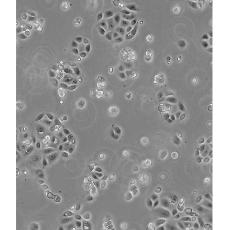

SW 1990

中文名稱 人胰腺癌細(xì)胞

生長特性 adhere

形態(tài)特征 epithelial

細(xì)胞描述 1978年從胰腺外分泌腺的胰腺腺癌II期患者的脾轉(zhuǎn)移灶中建立了SW 1990細(xì)胞株。 報(bào)道該細(xì)胞的植板率為29%。